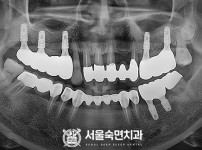

임플란트-전후사진3

임플란트-전후사진4

치과를-선택할-때-꼭-확인하세요-서울숙면치과-임플란트-전후사진